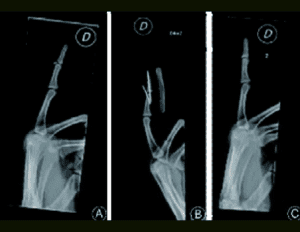

Fixation method for unstable bony mallet finger

A simple fixation method for unstable bony mallet finger A…